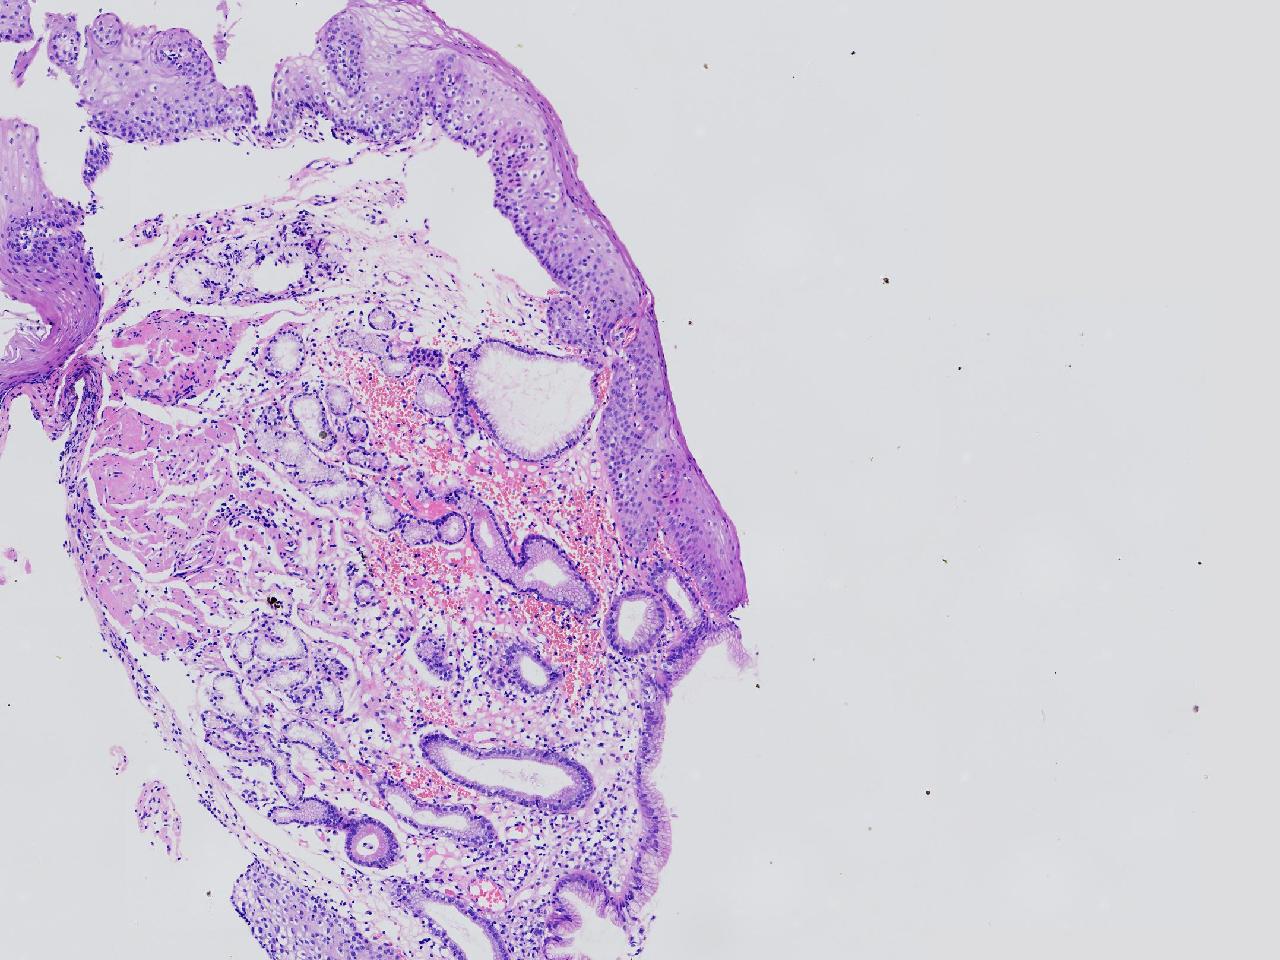

女,38岁,食管距门齿38cm处见一扁平隆起,表面粗糙,活检1块,质软,弹性可。

食管活检

灰白色不整形软组织1块,直径0.2厘米。

结合取材部位排除Barrett食管

粘膜慢性炎。

Barrett食管,粘膜慢性炎。